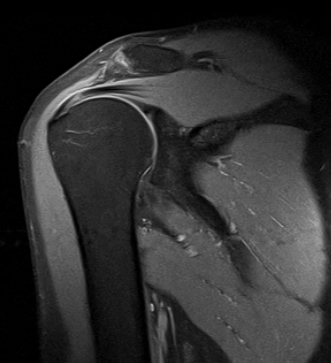

La Resonancia magnética (RMN) es un método de imagen multiplanar no invasivo, basado en la interacción entre la radiofrecuencia, los campos magnéticos y ciertos núcleos en el cuerpo humano (generalmente núcleos de hidrógeno del agua), después que el cuerpo ha sido introducido en un campo magnético fuerte. La información obtenida es procesada por un ordenador y transformada en imágenes del cuerpo humano.

La RM consigue información sobre la estructura del cuerpo permitiendo diferenciar entre tejidos normales y anormales lo que la convierte en una técnica muy sensible para detectar enfermedad. Esta sensibilidad está basada en un alto grado de contraste debido a las variaciones en las propiedades de relajación magnética de los diferentes tejidos, tanto normales como anormales.